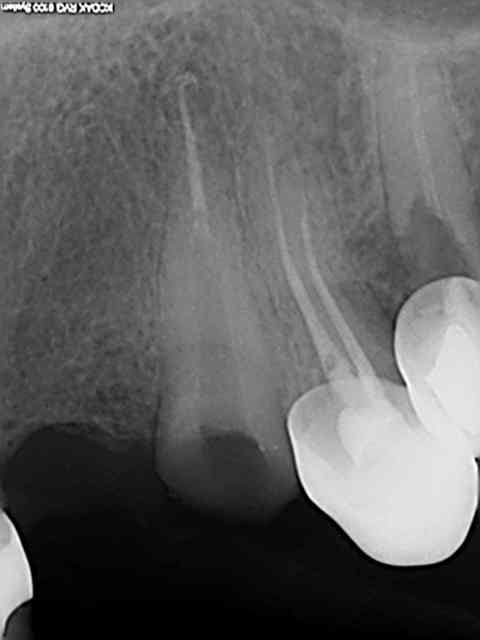

J'ai reposté quelques radios de biopulpectomies

RTE dans un précédent post...